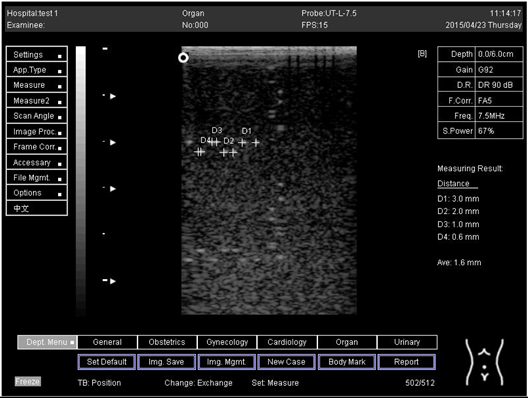

5.0Axial resolution

Biomimetics 07 00130 i011

D1 = 3.0

D2 = 2.0

D3 = 1.0

D4 = 0.5

5.0 Lateral resolution

Biomimetics 07 00130 i012

Regarding phantom 2, only linear probes were applied. This is because phantom 2 is shorter than phantom 1, and the linear probe had a lower penetration setting compared to the curve probe. Therefore, a linear probe is more suitable for the phantom. Based on the results recorded on phantom 2, axial and lateral resolution measurements were still under an acceptable value since the percentage difference between the actual distances was less than 2% (Table 6).